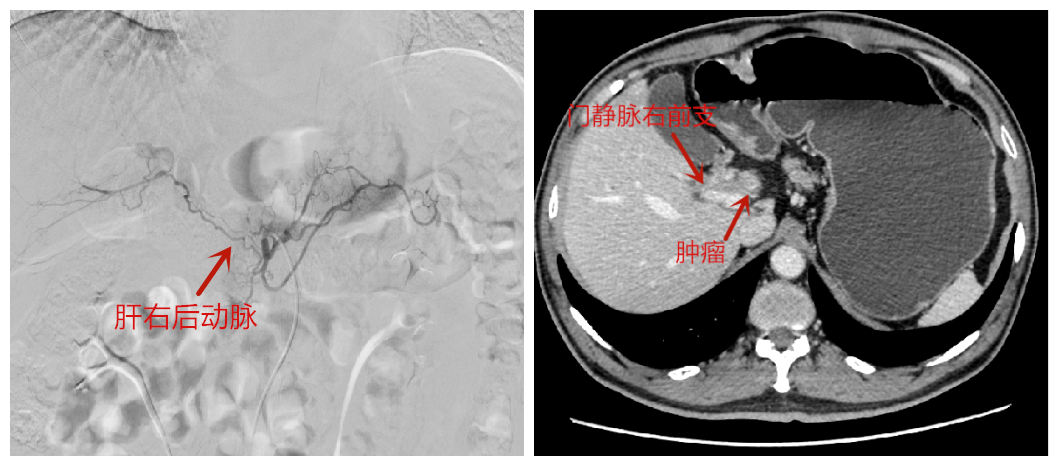

患者术前肝右后动脉(左)与门静脉(右)影像

患者来自河南,因体检被查出肝门部胆管癌,手术难度大,风险高,经当地医院推荐,他来到北京清华长庚医院项灿宏的门诊,寻求进一步治疗。完善全腹增强CT检查后发现,肿瘤已经侵犯了肝左外叶、左内叶、右前叶、门静脉与肝右后动脉,“手术不仅要完成肝左三区切除,还需要将被肿瘤侵犯了5厘米的肝右后动脉切除,往往这样的患者被认为是极难行根治手术的。”项灿宏说,而肝右后动脉承担着为肝右后叶供血的关键作用,若整个切除,有可能会导致肝脏因血流不足而肝脓肿、坏死甚至肝衰竭。“对肝胆胰外科医生来说,尽管肝门部胆管癌的左三区切除是肝切除手术的难关,但也要去勇于承担与挑战。”为此,项灿宏多次与具有肝移植、血管吻合经验丰富的副主任医师徐光勋沟通,最终拟订了手术方案:通过“搭桥”术,重建肝右后动脉。

而手术的难点远不在此。“为切除肿瘤,手术预计切除近60%的肝脏,要保障余肝具有足够的代偿功能。”项灿宏说。术前通过肝动脉造影等检查,明确肝脏影像与血供情况后,项灿宏首先行肝固有动脉栓塞,减少肝固有动脉血流,拓宽肝右后动脉通道,增大血流量;一周后再行门静脉右前支栓塞,减少已被肿瘤侵犯的肝脏血流,使其体积萎缩变小的同时,也使未被肿瘤侵犯的肝右后叶体积慢慢增生,保证术后有足够良好的肝体积。